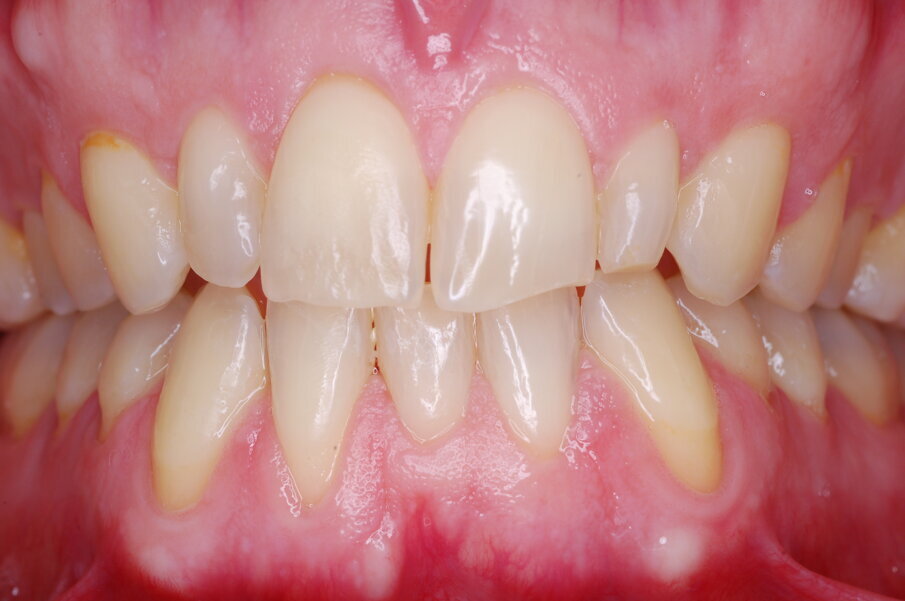

Diagnosi ed eziologia Un uomo sano di 39 anni si è presentato nel nostro studio ortodontico lamentando un aspetto dentale poco attraente e la paura della chirurgia ortognatica proposta da un altro ortodontista. Clinicamente, il profilo del paziente era rettilineo e la vista frontale non mostrava alcuna asimmetria facciale. L’esame funzionale non ha rivelato alcuna deviazione mandibolare o riduzione dei movimenti. Il paziente non aveva dolori articolari e non sono stati rilevati rumori articolari. Era presente una lieve occlusione molare bilaterale di Classe II, un morso aperto e un grave affollamento in entrambe le arcate. L’affollamento era particolarmente grave nell’arcata mandibolare, sebbene mancasse l’incisivo centrale mandibolare destro. Gli incisivi mascellari erano di piccole dimensioni, suggerendo una discrepanza dell’indice di Bolton se fossero stati presenti tutti e quattro gli incisivi mandibolari. Erano inoltre presenti un morso incrociato nella regione dell’incisivo laterale superiore sinistro e una grave rotazione distale del secondo premolare mandibolare sinistro (Figg. 1-8).

Figg. 1-8_Fotografie facciali e intraorali pre-trattamento.